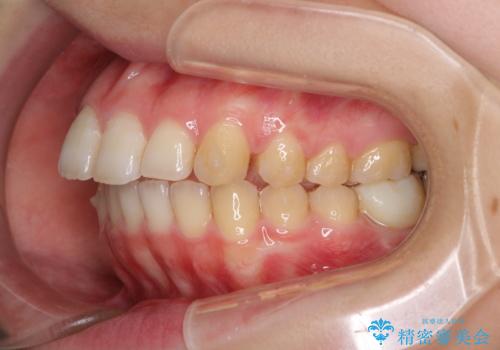

- 口の閉じにくさと割れてしまった奥歯を気にして来院された患者様です。

IPR(歯と歯の間を削る)と歯列全体の後方移動によって口元が引っ込むように設計し、インビザラインにより治療を行うこととしました。

割れてしまった奥歯は抜歯し、矯正治療中の良いタイミングでインプラントを埋入することとしました。

インプラントは、治療期間を短くすることが可能な、ストローマン社のSLActiveを使用することとしました。

上下正中がずれていたため、抜歯による矯正治療も検討しましたが、口元がそれほど突出していなかったため、非抜歯にて矯正することになりました。

その結果正中のズレは残りましたが、口を閉じたときの感覚や奥歯の咬み合わせには全く問題なく、患者様には大変満足していただきました。